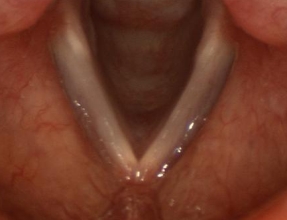

The vocal folds have a V-shape, and are covered by a soft elastic lining called the mucosa that can vibrate at high speeds. Ordinary voice production happens when the vocal folds meet completely in the middle; the lungs blow air against vocal folds that are closed, but more loosely than they would be during swallowing. Air pushes through the small space between them, making the mucosa covering the vocal folds vibrate.

This is the venturi effect. As air passes through a constriction (a 'venturi'), it speeds up and creates a suction behind it. This suction pulls at the mucosa from each vocal fold, which meet in the middle, only to be pushed aside by more air from the lungs. This cycle creates a repeating vibration that is very fast. The vibration produces sound.